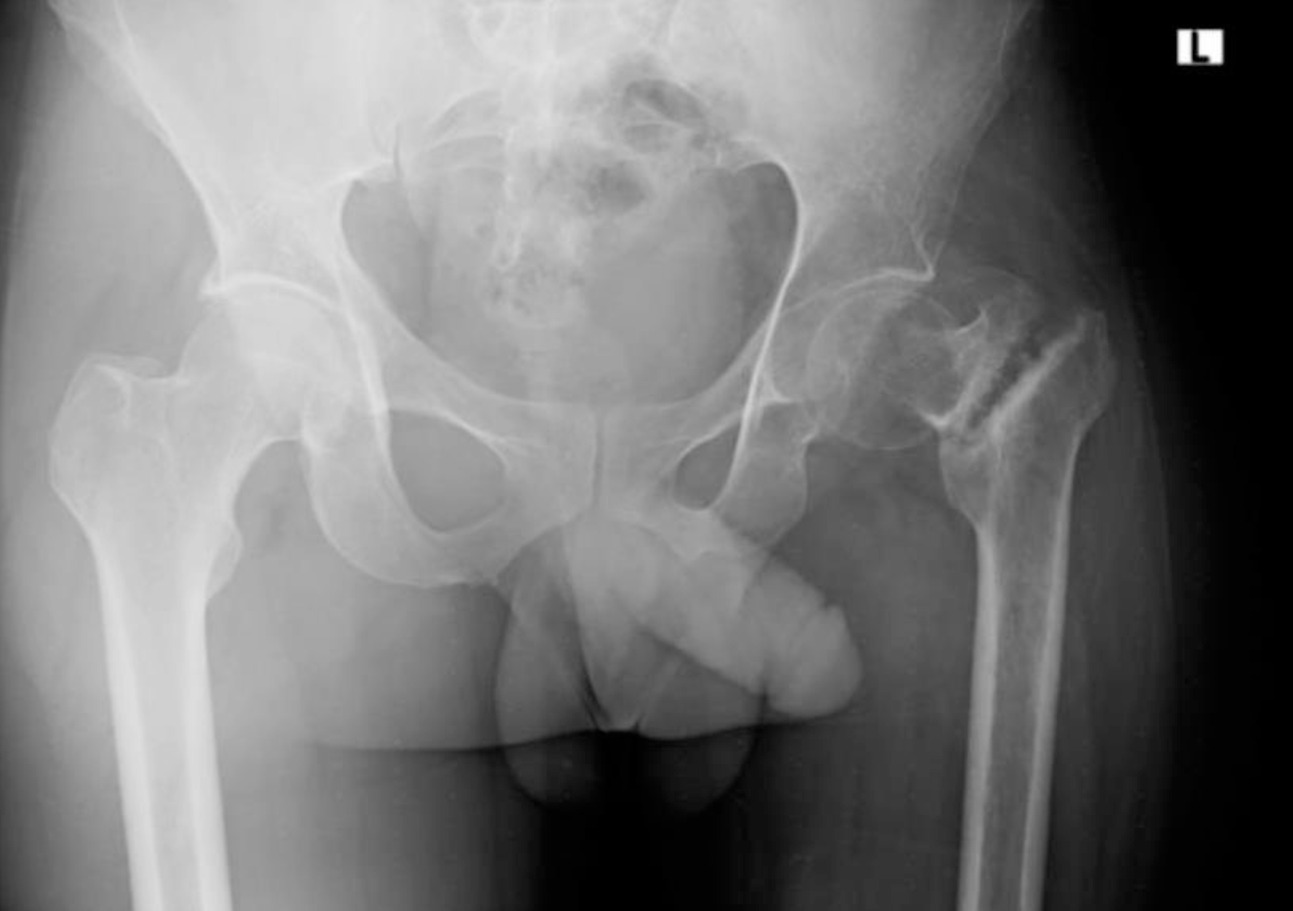

Upon examination, the patient was unable to bear weight on his affected limb, with a painful mobility at the fracture site. The left lower extremity was shortened with an externally rotated posture. Anterior posterior (AP) X-ray of the pelvis showed an ununited intertrochanteric fracture with sclerosed margins and no evidence of callus or bridging trabeculae (Figure 1). Vitamin D level was not assessed due to financial cost limitation but other labs were unremarkable, and he was admitted for surgical fixation with a diagnosis of primary intertrochanteric nonunion.

On examination, her right leg was observed to be shortened, with a leg length discrepancy of 4.5 cm, and it was positioned in an externally rotated attitude. She also exhibited tenderness in the hip area. Laboratory tests yielded unremarkable results. An X-ray of the pelvis showed an intertrochanteric nonunion, characterized by rounded, blunted fracture ends and osteopenia of the right femur, with superior migration of the distal fragment (Figure 4). She was subsequently admitted for internal fixation, with a diagnosis of right primary intertrochanteric nonunion.